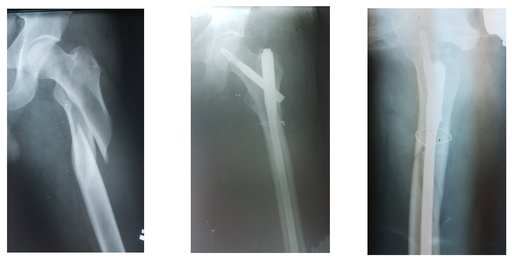

При переломах стегнової кістки, які найчастіше трапляються у людей похилого віку проводиться операційне втручання із застосуванням імплантів типу PFNA, PFNAL, протезування кульшового суглобу що дозволяє хворому на 2-3 добу після оперативного втручання пересуватися самостійно.

При травмах в\3 стегнової кістки та с\3 стегна застосовуються сучасні блокуючі інтрамедулярні системи що дозволяють на 2-3тю добу пересуватися